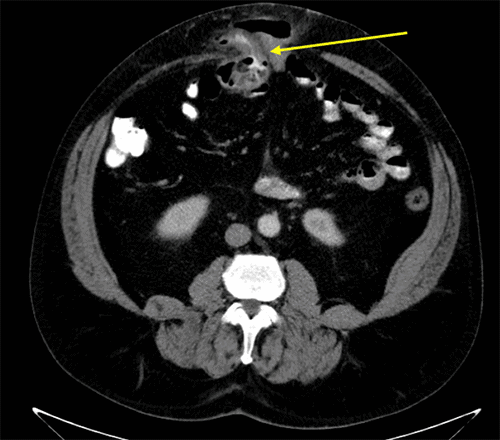

A 62-year-old male presented with a complex abdominal emergency rooted in a remote history of trauma and chronic comorbidities. His past medical history was notable for chronic obstructive pulmonary disease, obstructive sleep apnea, type 2 diabetes mellitus (HbA1c 6.6%), obesity (BMI 40.52 kg/m²), and an extensive 60 pack-year smoking history. His surgical history began in 1982 with an exploratory laparotomy for a liver laceration sustained in a motor vehicle crash, from which he had an uneventful initial recovery. Decades later, in 2019, he presented to a local hospital with acute abdominal pain, an enlarging abdominal bulge, and nausea. A computed tomography (CT) scan at that time revealed a ventral hernia containing incarcerated bowel, without radiographic evidence of ischemia or strangulation (Figure 1). The hernia was successfully reduced manually in the emergency department, and he was discharged with outpatient general surgery follow-up.

Figure 1. Initial Computed Tomography of Ventral Hernia (October 2019). Published with Permission

Axial CT scan from October 24, 2019, demonstrating the patient’s chronic ventral abdominal wall hernia. The image shows bowel loops and their associated mesentery (arrow) incarcerated within the hernia sac, without radiographic evidence of strangulation or perforation at that time